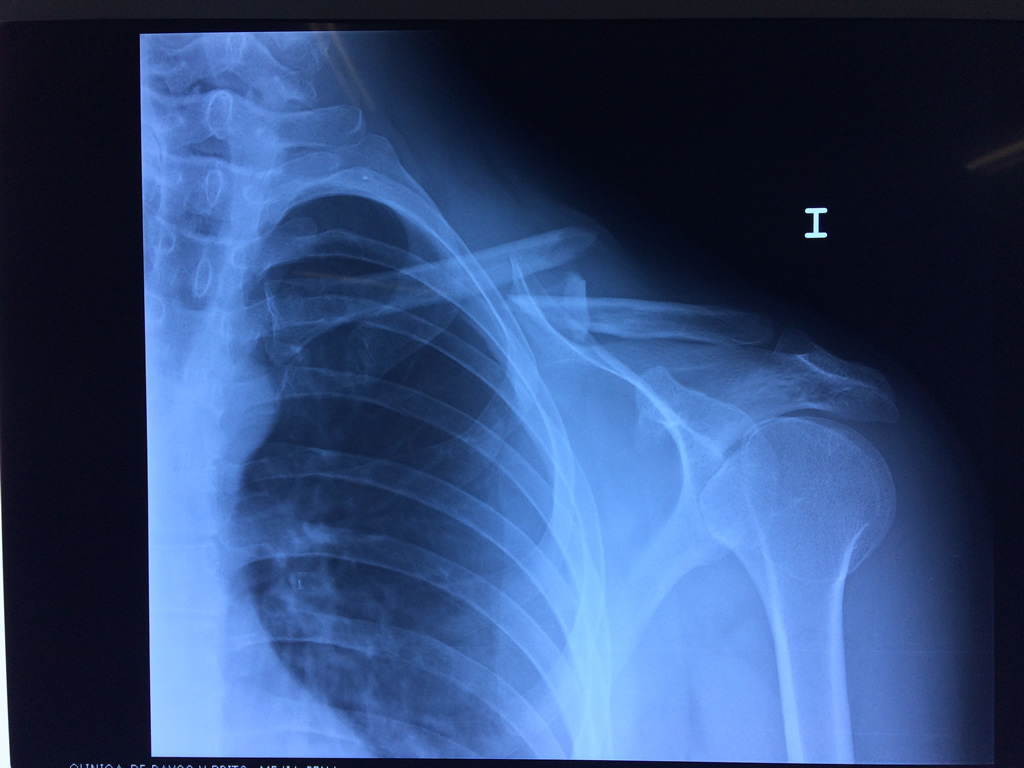

Cirugía de Fémur - Clavícula

La clavícula es un hueso largo, con forma de "S" itálica, situado en la parte anterosuperior del tórax. Junto con la escápula forman la cintura escapular. Se puede palpar por toda su longitud y se extiende del esternón al acromion de la escápula, siguiendo una dirección oblicua lateral y posterior.

Se considera el único medio de unión entre el miembro superior y el tórax. A pesar de su aspecto, similar al de un hueso largo, posee una estructura semejante a la de un hueso plano, ya que carece de epífisis y de diáfisis, lo que la harían entrar dentro de la clasificación de hueso largo. Carece de un canal medular propiamente dicho.